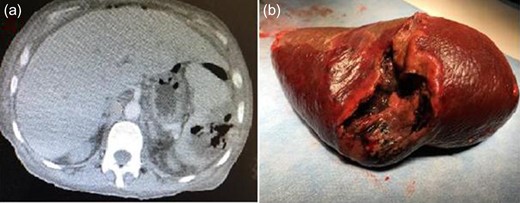

A 55-year-old female patient was examined in the emergency department with abdominal pain that had been persistent for ~10 days and having been aggravated for the last 3–4 days. Her past history was notable for diabetes mellitus (DM) for ~25 years. Additionally, she had undergone a coronary by-pass operation 10 years ago and a left infrapatellar amputation 4 years ago. Chronic renal failure had been diagnosed 2 years ago and she had been receiving hemodialysis treatment three times a week for the last 1 year. She had no history of abdominal trauma. Laboratory tests resulted with; White Blood Cell: 15 100/mm3, Hemoglobin: 8.5 g/dL, C-reactive protein: 40 mg/dL, Urea: 37.9 mg/dL, Creatinine: 2.25 mg/dL, Albumin: 2.4 g/dL, Sodium: 134 mmol/L, Potassium: 3.1 mmol/L, Calcium: 7.9 mg/dL, Glucose: 329 mg/dL and other biochemical parameters were normal. The abdomen was diffusely tender, and she also had guarding and rebound tenderness during the physical examination. Blood temperature was 38.7°C. An abdominal ultrasonography (US) showed diffuse intraabdominal free fluid collection. On an abdominal computed tomography (CT) there were free fluid collections in all abdominal quadrants; there also existed intraabdominal minimal free air images. There were air-fluid images in the splenic parenchyma (abscess?, perforation?) (Fig. 1a). The radiology department reported that it may be a gastrointestinal perforation. Based on the current findings, the patient was urgently operated according for a preliminary diagnosis of acute abdomen. Intraabdominal seropurulent fluid of ~2000 ml was aspirated perioperatively. There were diffuse fibrin matrixes in the entire peritoneum. No intestinal perforation was noted during exploration. There was a perforated abscess pouch with a size of ~8 × 6 cm2, which expanded posteriorly from splenic hilus and partly contained necrotic foci (Fig. 1b). Splenectomy and drainage were performed and the abdominal cavity was irrigated with abundant isotonic saline. Patient was postoperatively monitored in intubated state at intensive care unit. No proliferation occurred in her blood culture. Escherichia coli was isolated from the abscess culture, however, and Meropenem 500 mg I.V. (three times a day) and Metronidazole 500 mg I.V. (three times a day) treatment was commenced as recommended by the infectious diseases department. Her dialysis program was maintained according to blood parameters. The patient died on postoperative Day 25 due to septic shock and multiple organ failure. Histopathologic examination revealed suppurative inflammation and abscess formation of the splenic tissue (Fig. 2). Informed consent was obtained from her son who participated in this case.

Abdominal computed tomography scan showing splenic abscess (a), the macroscopic view of the splenectomy specimen (b).